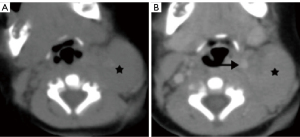

Lymphadenopathy is the most common pathology of the carotid space. A variety of primary diseases such as lymphoma, inflammation, and secondary diseases such as metastatic lymphadenopathy may involve lymph nodes, manifesting as masses of the carotid space. Enlarged lymph nodes, especially a solitary node, may mimic a primary tumor on CT and MRI. So, although the majority of lymphadenopathy is caused by metastatic tumors, we still describe them as “primary masses”. The imaging findings of diseased lymph nodes vary with different pathologies. Lymphoma may occur at any age with no gender difference, typically manifesting as painless or growing lymphadenopathy, and may have varying enhancement on CT/MRI imaging with extensive involvement and important neck structures encased yet without narrowing of arterial lumen (28-30). Metastatic lymphadenopathy is more frequently seen in middle-aged and elderly males and usually caused by head/neck squamous cell carcinoma, thyroid cancer, and so on. On CT/MRI imaging, it usually manifests as circular enhancement with central necrosis (squamous cell carcinoma), or obvious enhancement with cystic changes or calcification (thyroid cancer) (31-33). Lymph nodes in the carotid space lie anterior, lateral, and posterior to the jugular vein throughout its course in the neck (34). Therefore, enlarged lymph nodes in the carotid space will not be medial to any vessel in the carotid space (Figure 13), which is different from neurogenic tumors.